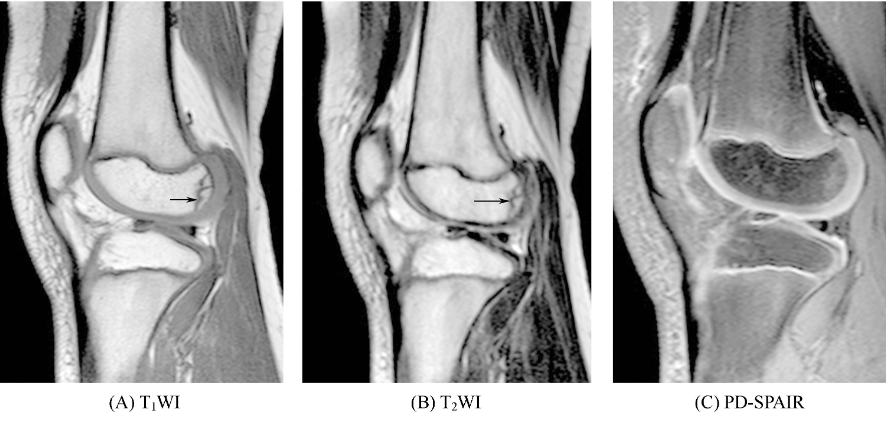

①长骨骨折一般不做MRI检查,其在显示骨折线方面不及CT,但可清晰显示骨折断端及周围出血、水肿和软组织损伤情况。骨折线在T1WI及T2WI上均表现为线状低信号影,其周围可见边界模糊的T1WI低信号及T2WI高信号影,为骨折后骨髓内的水肿或渗出改变(图1)。MRI不能反映皮质骨内骨折线,但若发生骨折端分离,可见低信号骨皮质内有条形或不规则中等信号或高信号改变,为出血所致。如骨折靠近关节,可见关节内积液。

图1 长骨骨折(A)、(B)示股骨外侧髁骨骺可见条状长T1短T2信号影,(C)PD-SPAIR(质子密度脂肪抑制序列)示邻近骨质呈高信号水肿改变。